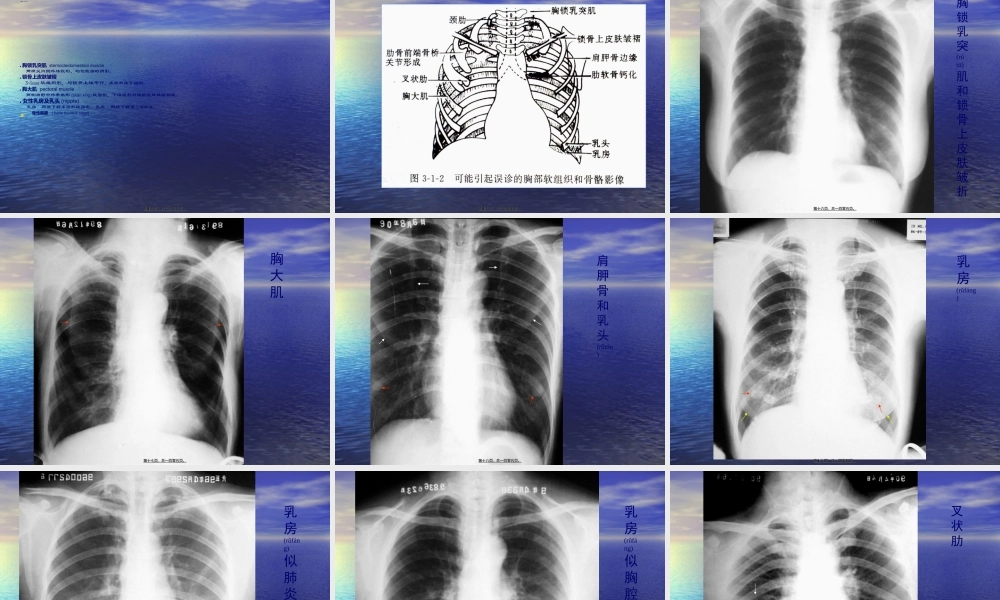

胸部普通(pǔtōng)X线影像诊断学Diagnosticimageologyofchestdiseases第一页,共一百零五页。第一页,共一百零五页。第一章呼吸系统(hūxīxìtǒnɡ)Respiratorysystem特点:含有空气,良好自然对比;病变密度增加或降低;第二页,共一百零五页。第二页,共一百零五页。第一节第一节XX线检查线检查(jiǎnchá)(jiǎnchá)技技术术TechniquesofX-rayTechniquesofX-ray常规常规(chángguī)(chángguī)XX线技术;线技术;胸部胸部CTCT技术;技术;胸部胸部MRIMRI技术;技术;胸部超声技术。胸部超声技术。第三页,共一百零五页。第三页,共一百零五页。一、普通(pǔtōng)检查Conventionalexamination(一)胸部透视(chestfluoroscopy)(二)胸部摄影:(chestradiography)第四页,共一百零五页。第四页,共一百零五页。透视时,荧光屏上的影像以黑色表示高密度物质(wùzhì);以白色透亮表示低密度物质(wùzhì)第五页,共一百零五页。第五页,共一百零五页。第六页,共一百零五页。第六页,共一百零五页。(三)、数字化X线摄影(shèyǐng)包括CR和DR,优点:图像清晰度提高;X线的接受剂量降低;影像存储传输(PACS)及远程医疗服务(fúwù);图像后处理,图片校正及减少重拍率。CR(computedradiography,CR)摄像板(IP)代替X线胶片。X线影像→读取装置→数字信号→后处理→数字信号→光信号→激光照相机→CR像片。高曝光宽容度,低辐射及可调节显示窗。DR(digitalradiography,DR)专用计算机直接读取感应介质记录到的X线影像信息→数字化图像重放和记录。资料快速、准确光速传输,可行PACS与网络影像学。第七页,共一百零五页。第七页,共一百零五页。第八页,共一百零五页。第八页,共一百零五页。二、几种不常用检查方法Severaluncommonmethods(一)高千伏摄影(highkilovotageradiography)(yǐshàng)第九页,共一百零五页。第九页,共一百零五页。第十页,共一百零五页。第十页,共一百零五页。(二)断层摄影(二)断层摄影((tomography)tomography)某一选定层面清晰,非选定层面模糊某一选定层面清晰,非选定层面模糊(móhu)(móhu)。主要用于肺。主要用于肺门与支气管病变、肺内占位以及空洞病变的诊断和鉴别诊断。已逐门与支气管病变、肺内占位以及空洞病变的诊断和鉴别诊断。已逐渐被渐被CTCT取代。取代。(三)支气管造影(三)支气管造影((bronchography)bronchography)采用人工对比的方法,通过气管插管,将对比剂采用人工对比的方...